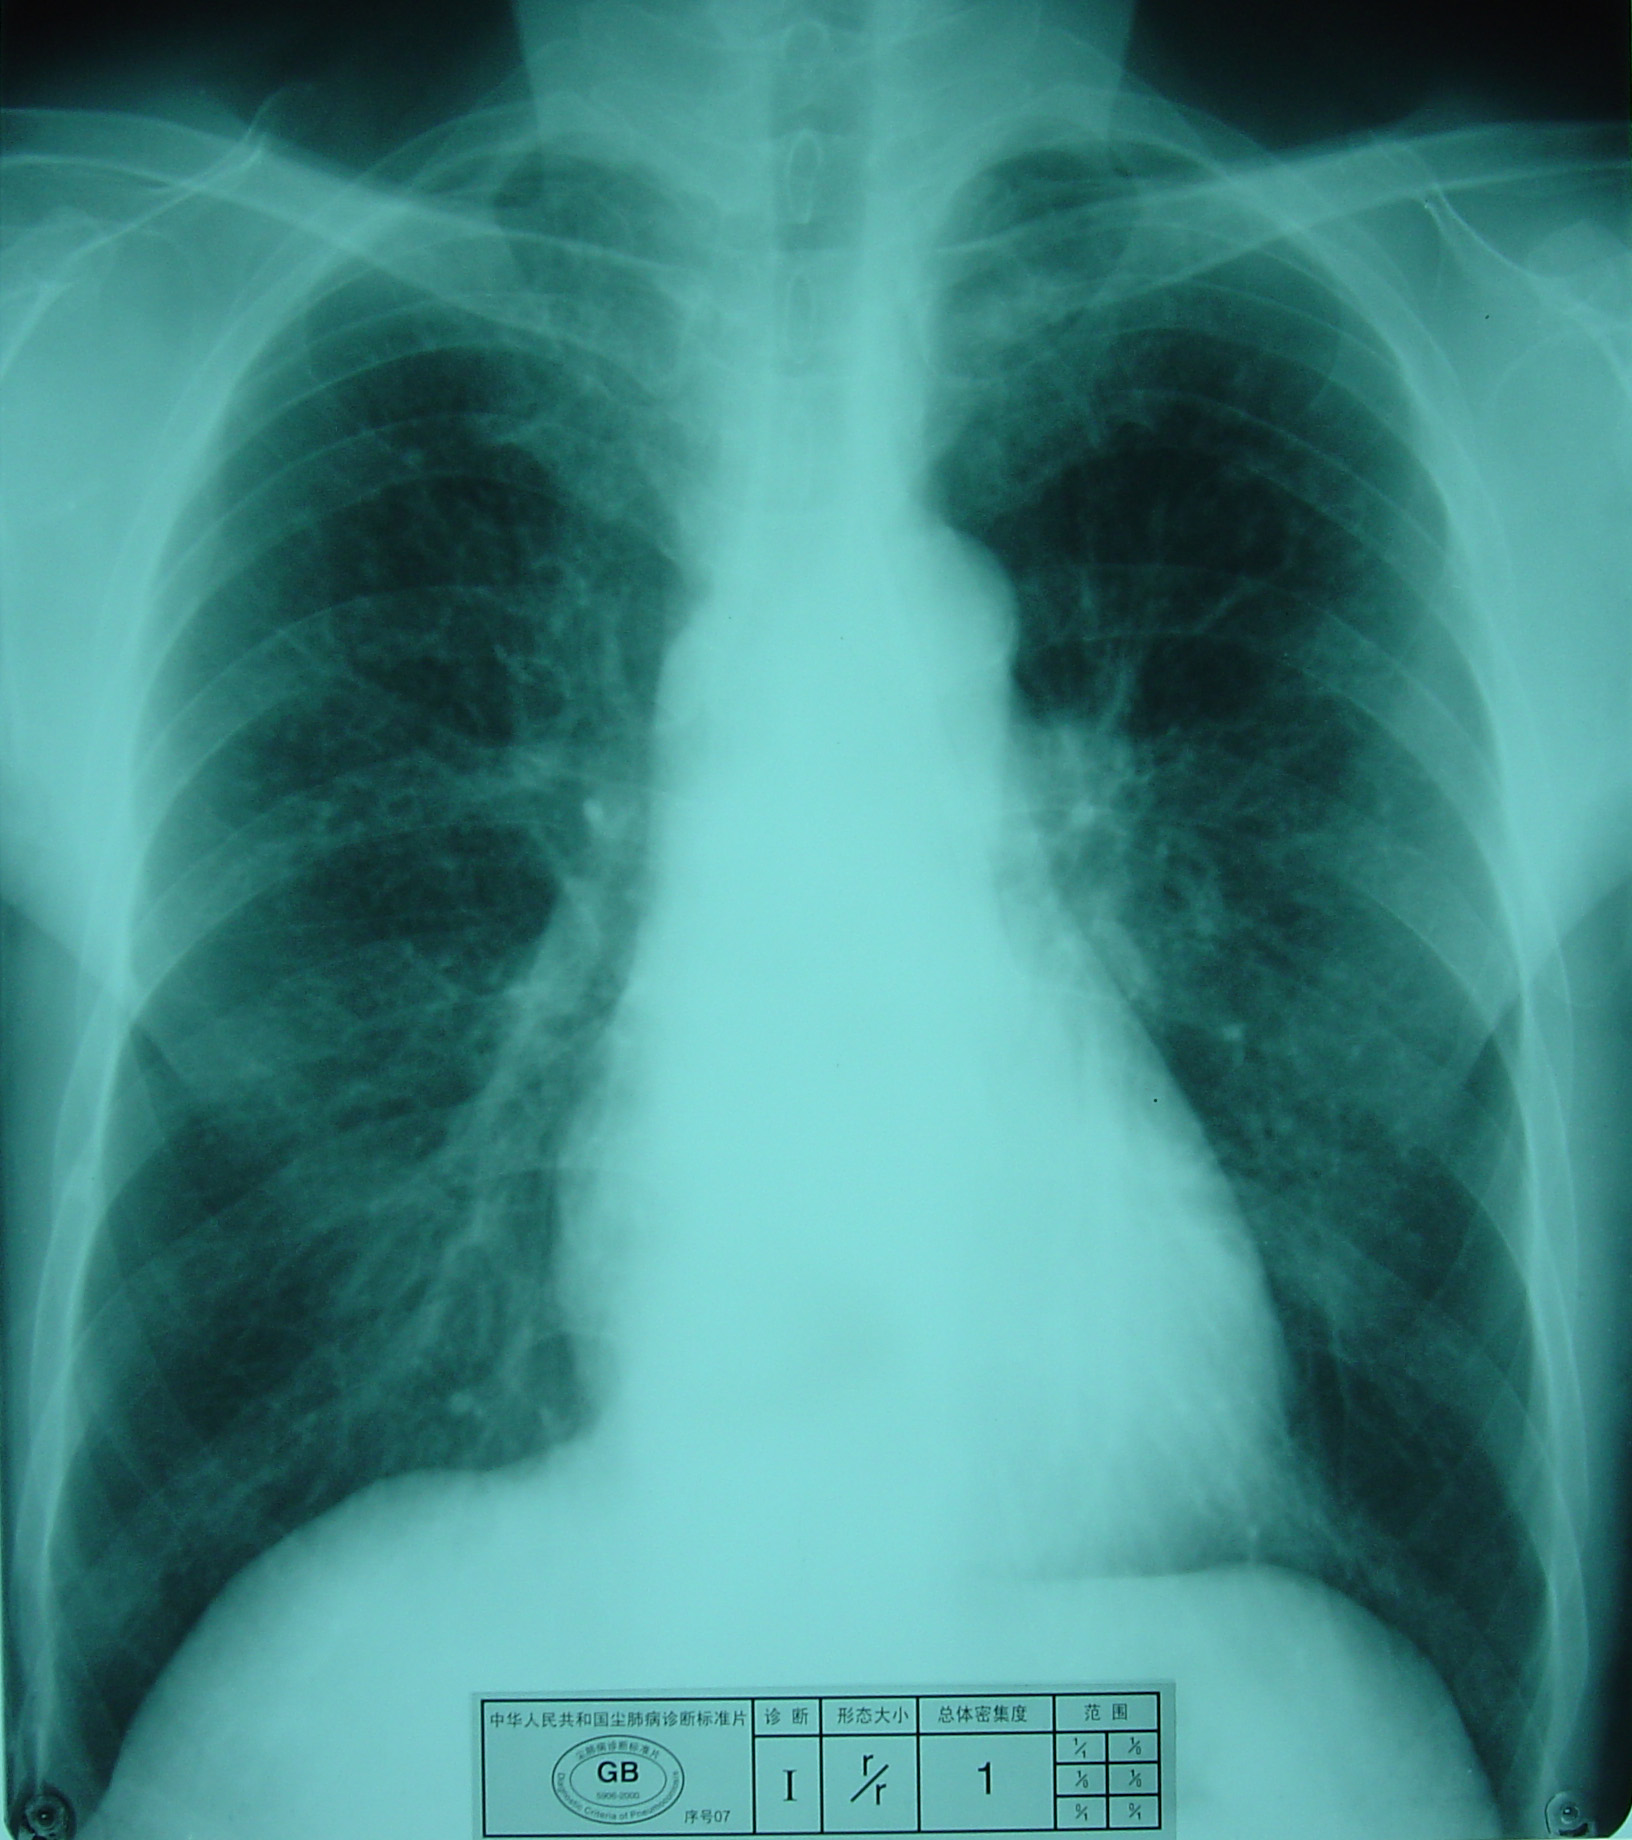

(2)X射线胸片表现:矽肺X射线胸片影像是肺组织矽肺病理形态在X射线胸片的反映,是“形”和“影”的关系,与肺内粉尘蓄积、肺组织纤维化的病变程度有一定相关关系,但由于多种原因的影响,并非完全一致。这种X射线胸片改变表现为X射线通过病变组织和正常组织对X射线吸收率的变化,呈现发“白”的圆形或不规则形小阴影,作为矽肺诊断依据。X射线胸片上其他影像,如肺门变化、肺气肿、肺纹理和胸膜变化,对矽肺诊断也有参考价值。在X射线胸片上,肺野内直径或宽度不超过10mm的阴影。小阴影按其形成分为圆形和不规则形两类。

1)圆形小阴影:是矽肺最常见和最重要的一种X线表现形态,其病理基础以结节型矽肺为主,呈圆或近似圆形,边缘整齐或不整齐,直径小于10mm,按直径大小分为p(<1.5mm)、q(1.5~3.0mm)、r(3.0~10mm)三种类型。p类小阴影主要是不太成熟的矽结节或非结节性纤维化灶的影像,q、r类小阴影主要是成熟和较成熟的矽结节,或为若干个小矽结节的影像重叠。圆形小阴影早期多分布在两肺中下区,随病变进展,数量增多,直径增大,密集度增加,波及两上肺区。

圆形小阴影(p类小阴影)

尘肺壹期:有下列表现之一者:

a)有总体密集度1级的小阴影,分布范围至少达到2个肺区。

尘肺壹期

尘肺壹期

尘肺壹期

尘肺壹期

尘肺壹期